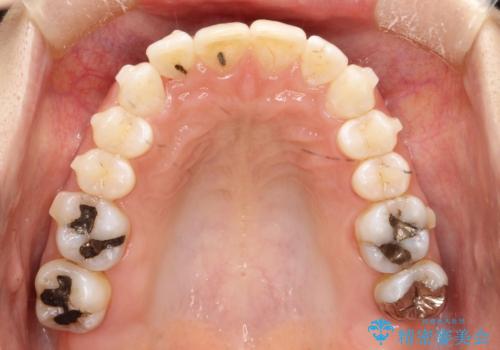

- 前歯のがたつきを気にされて来院されました。

右上の前から2番目の歯が前方に大きく傾いており、下の前歯もガタガタしていました。

インビザラインにて、歯と歯のあいだをわずかに削り並べる計画としました。

しっかりとマウスピースを使用していただけたので、順調に治療を終えることができました